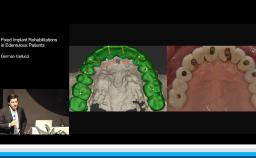

Ceramic materials are increasingly used for the fabrication of dental reconstructions. However, because there are so many options for fabricating ceramic prostheses, the selection of an ‘ideal’ material is becoming more and more complex. This lecture presents concepts for choosing the type of reconstruction, material, and method of fabrication for a highly esthetic outcome. Long-term survival rates, advantages, and limitations for new ceramic methods and materials - in particular high-strength ceramic zirconia - are presented in this lecture. The results of clinical studies comparing digital CAD/CAM and conventional workflows for fabrication of all-ceramic restorations are also presented.